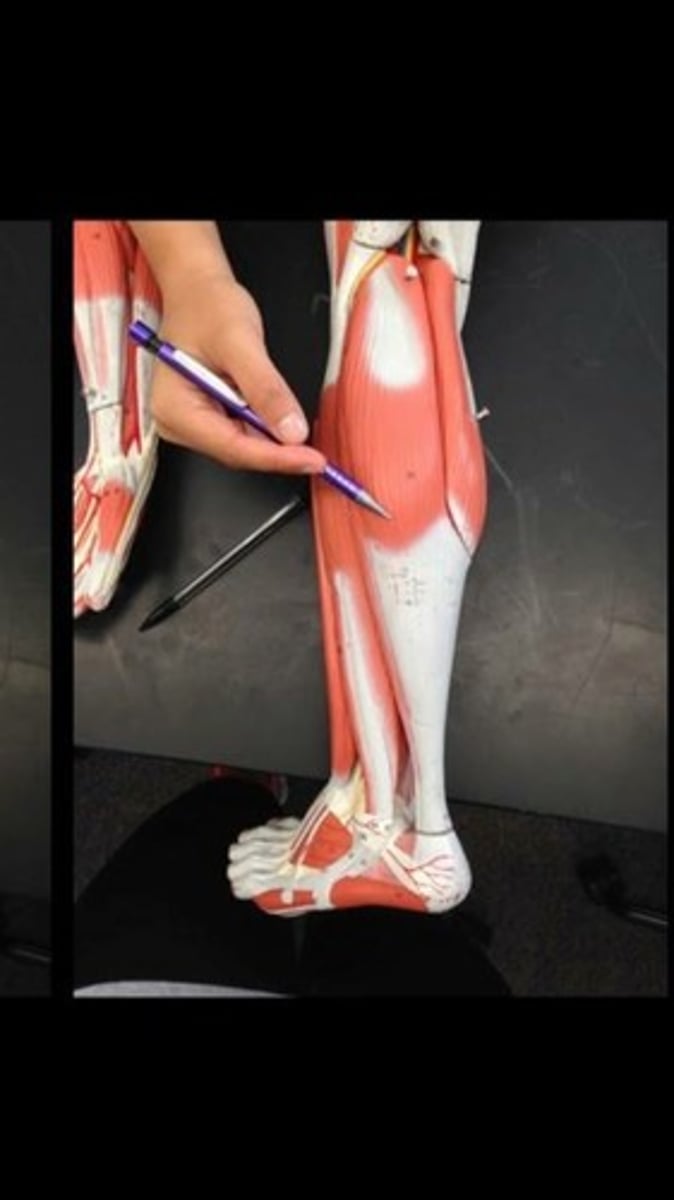

Gastrocnemius lateral head

Gastrocnemius medial head

Soleus

Flexor hallucis longus